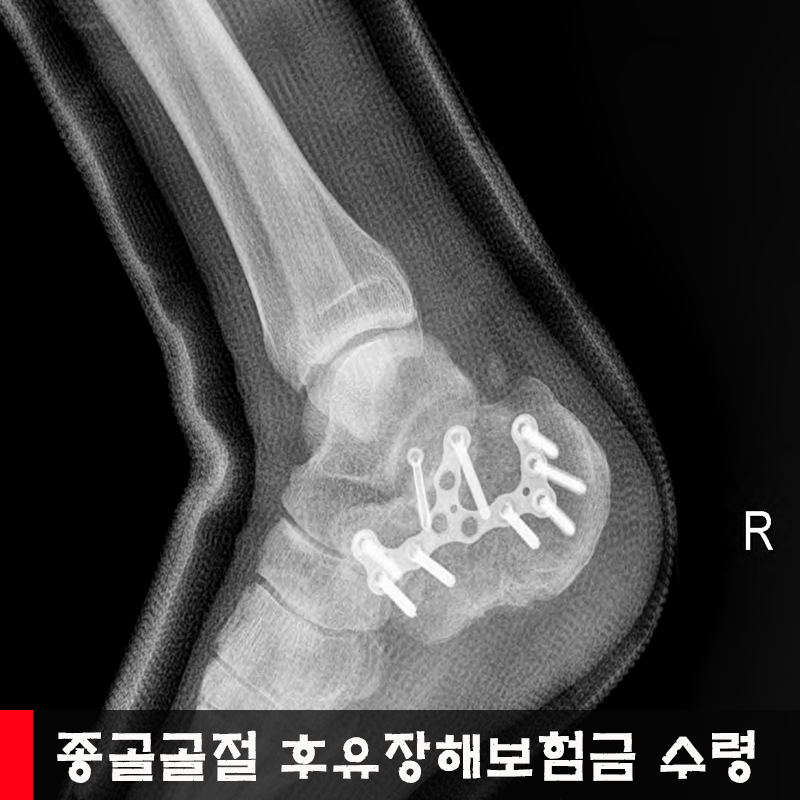

K¾¾´Â 0000³â 0¿ù 0ÀÏ, ¾à 3M ³ôÀÌ »ç´Ù¸®¿¡¼ Ãß¶ôÇÑ »ç°í·Î 00º´¿ø ÀÀ±Þ½Ç°æ¿ì, ÁÂÃø Á¾°ñ °üÀý³» ºÐ¼â°ñÀý ¹× ¼ö¼úÈÄ ¿°Áõ ¹× °ñ¼ö¿° Áø´ÜÇÏ¿¡ ÁÂÃø °üÇ÷Àû Á¤º¹¼ú ¹× ±Ý¼ÓÆÇ °íÁ¤¼ú ½ÃÇà¿´°í, ±Ý¼ÓÆÇÁ¦°Å¼úÀ» 00³â 0¿ù 0ÀÏ º´¿ø¿¡¼ ½ÃÇàÇÏ¿´½À´Ï´Ù. ÀÌÈÄ ÇǺΠ¹× ¿¬ºÎÁ¶Á÷ ±«»ç¿¡ ´ëÇÑ ÇÇÆÇÀ̽ļúµµ ÀÌÈÄ ½ÃÇàÇÏ°Ô µÇ¾ú½À´Ï´Ù.

ÁÂÃø Á·°üÀý ¹è±¼ -10, Àú±¼20, ³»¹ø15, ¿Ü¹ø20, ÃÑÇÕ°è 45 /120

¿ìÃø Á·°üÀý ¹è±¼ -5, Àú±¼ 20, ³»¹ø15,¿Ü¹ø20, ÃÑÇÕ°è 50/120